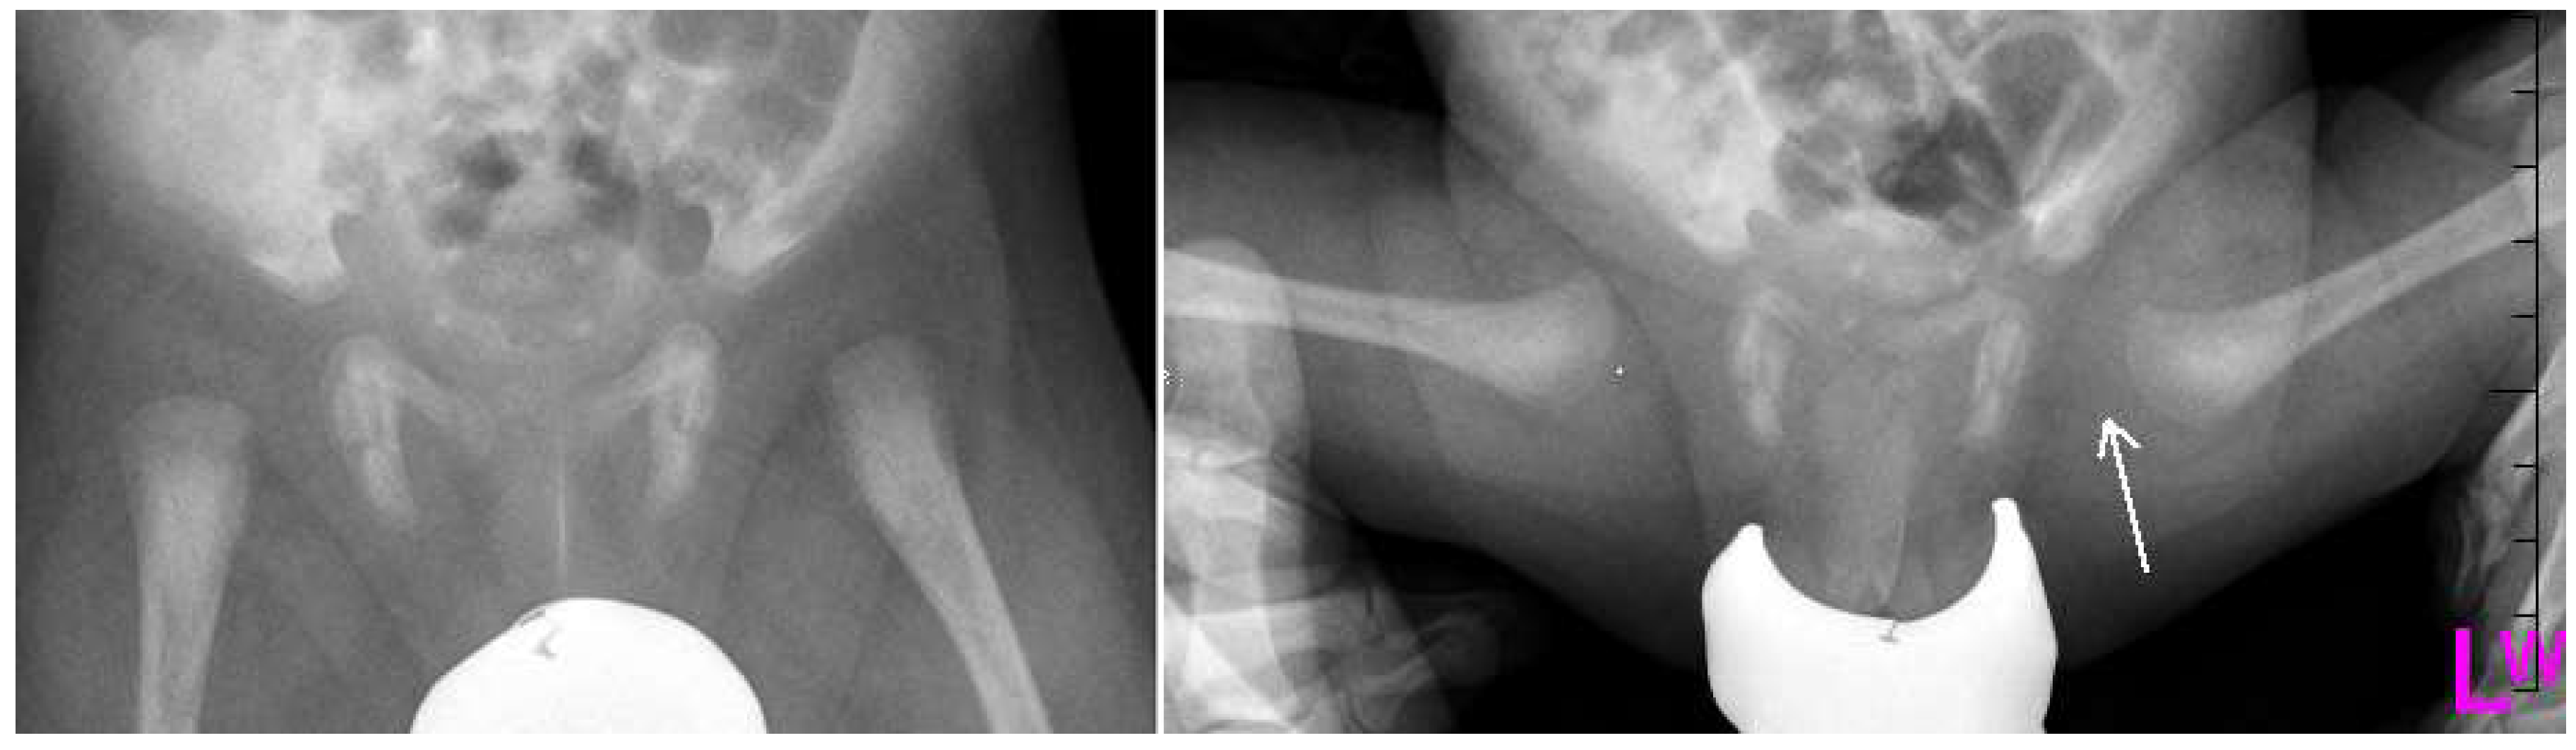

Figure 2.

Radiographs: Antero-posterior (AP) and Lauensteun view of three weeks old child’s left hip, slightly out of the socket (eccentric hip).